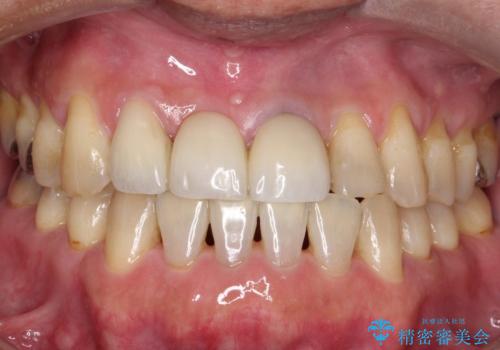

歯周病が進行してしまった歯に対し、再生治療および歯周補綴を行うことで歯周組織の安定を得ることができました。

再生治療後、歯周補綴を行っております。